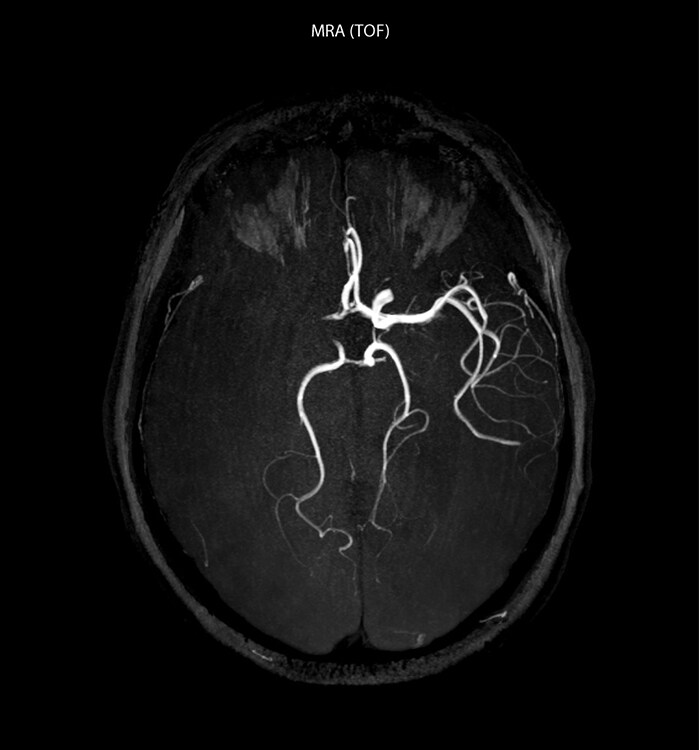

MRI is widely used for visualizing primary brain tumors and secondary lesions in oncology patients. Its excellent soft tissue contrast and functional imaging provide radiologists information on the location, size, morphology, composition and physiology of lesions to help them in diagnosing and staging. Still, there are cases where radiologists would like to have additional capabilities for their diagnosis, for instance in distinguishing high-grade and low-grade tumors with more confidence and ultimately for performing the numerous follow-up MRI exams without contrast administration in children after brain tumor resection.